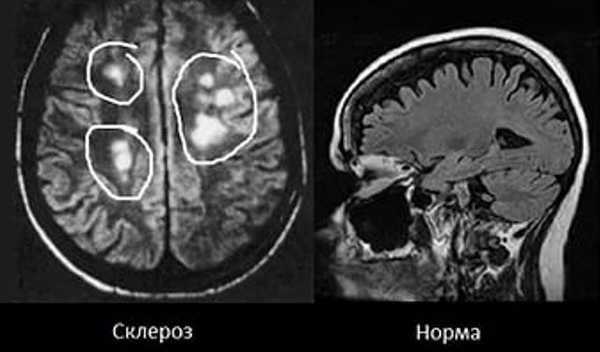

Признаки атеросклероза (пораженные участки указаны стрелками) на МРТ

Рассеянный склероз на МРТ

При рассеянном склерозе разрушается миелиновая оболочка нервных волокон

Очаги рассеянного склероза на МРТ видны на любых, в том числе начальных, стадиях. Сканирование выявляет изменения разной степени давности: от “свежих”, сопровождающихся неврологическим дефицитом, до “застарелых”, при которых уже регрессировали клинические проявления. Для успешного лечения важно как можно раньше пройти обследование.

Рассеянный склероз на МРТ головного мозга выглядит как пятна округлой формы диаметром до 2 сантиметров, которые по мере развития патологии могут сливаться. Оттенок измененных участков зависит от стадии болезни и бывает светлым, темным или идентичным здоровым тканям (без контраста не выделяется).

Классическим признаком рассеянного склероза на МР-снимках головного мозга являются бляшки линейной формы, располагающиеся перпендикулярно боковым желудочкам. Их называют “пальцы Доусона”.